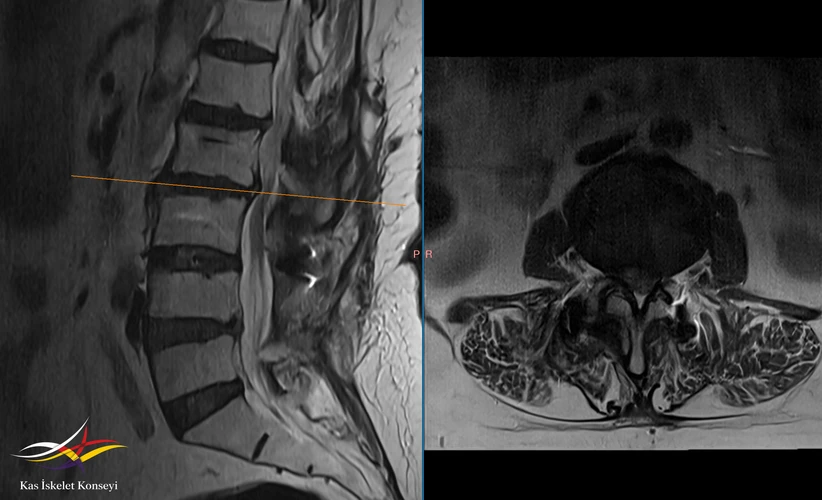

Resim 2. Lomber MRG: L2-3 seviyesinde rest stenoz görülmekte.